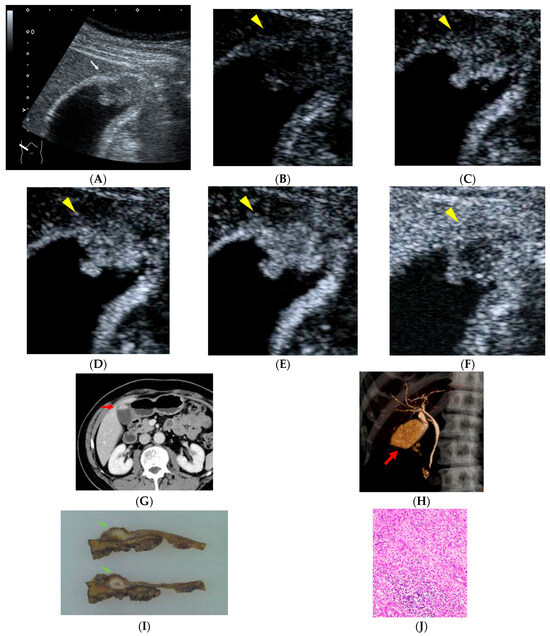

Figure 1.

A 66-year-old man with a history of rectal cancer surgery 19 years earlier. During follow-up, a polypoid lesion with a slightly hypoechoic center is detected at the fundus of the gallbladder, accompanied by irregularity of the gallbladder wall ((A), white arrow). On contrast-enhanced ultrasonography (CEUS), the polypoid lesion shows heterogeneous enhancement in the early phase followed by washout ((B), 0 s; (C), 18 s; (D), 19 s; (E), 22 s; (F), 300 s after injection of contrast material, yellow arrowheads). Contrast-enhanced abdominal CT demonstrated an enhancing polypoid lesion at the gallbladder fundus ((G), red arrow). CT cholangiography revealed a filling defect at the gallbladder fundus ((H), red arrow). Histopathological examination revealed gallbladder carcinoma composed of both well-differentiated and poorly differentiated adenocarcinoma components, with partial invasion into the liver bed, corresponding to stage IIIb disease ((I), green arrows; (J)). The patient has remained recurrence-free for 65 months after surgery.